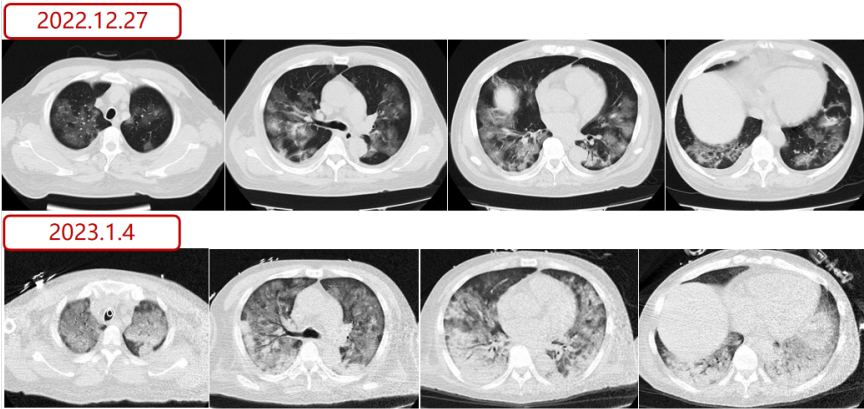

急诊胸部CT(12月27日)示双肺弥漫多发磨玻璃影,心包及双侧胸腔少量积液。小叶中心型肺气肿。

注:下图3月3日为评估肾移植时,12月27日为本院急诊时

入MICU第2天情况1月4日

预计短期内难以脱机,行气管切开术。复查影像学:肺部磨玻璃影的范围和密度较前加重。

图片